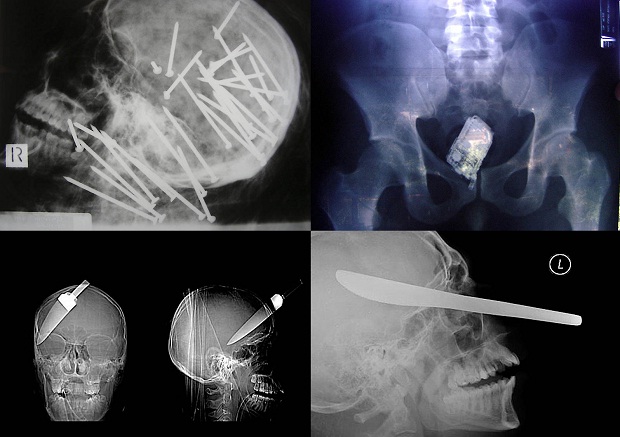

1. Череп китайца, которому в голову выстрелили пневматическим молотком.

14. Мобильник в кишечнике заключенного.

15. Нож в голове 10-летнего мальчика. Мальчик выжил.

18. 12-сантиметровый нож в черепе подростка.